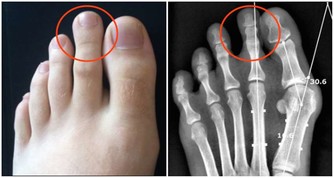

***2 吃飯快,不利口腔下顎發育***

細嚼慢嚥,對於孩子更為重要,因為涉及到下頜的發育和口腔護理。吃慢一點好,而且要兩邊都嚼一嚼,不然難免“大小臉”。